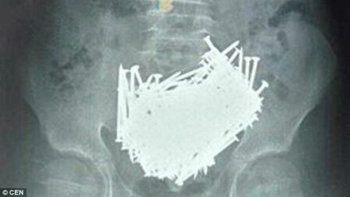

Mắc hội chứng dị thực: Cậu bé nuốt 200 cái đinh vào bụng trong một tháng

Vừa qua, sau khi chụp CT cho một cậu bé 15 tuổi, các bác sĩ ở Trung Quốc hoảng hốt khi thấy có tới 200 cái đinh nằm trong bụng.